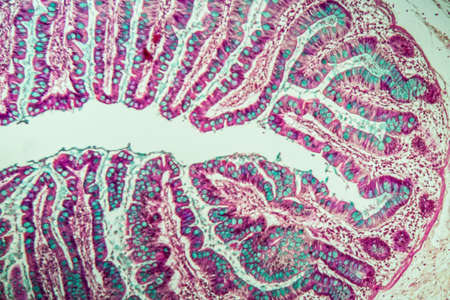

Small intestine with villi under the microscope 100x